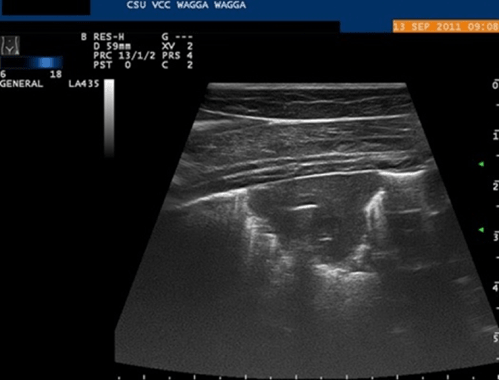

You perform an ultrasonographic examination of the lymph nodes: